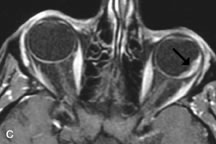

Inflammatory conditions of the orbit, both idiopathic (inflammatory pseudotumor) and those of known causes, have been found to be hypointense to fat and isointense to muscle on Tl-weighted studies and isointense or slightly hyperintense to fat on T2-weighted images (Fig. 21).50,64,69 The more fibrous or sclerosing varieties have less signal intensity on T2-weighted images. Marked enhancement is seen in pseudotumor infiltrates after gadolinium administration.70 The same signal characteristics are demonstrated in patients with Tolosa-Hunt syndrome, with mass lesions seen in the cavernous sinuses and orbital apices.71

Fig. 21. A. T1-weighted MR scan demonstrates diffuse enlargement of both the superior rectus and levator palpebrae superioris muscles (single arrows). The involvement of the tendinous insertions and preseptal soft tissues (open arrows) as well as lack of involvement of other muscles helps differentiate this entity from thyroid-associated orbitopathy. B and C. Postcontrast fat-suppressed T1-weighted MR scans demonstrate extensive enhancement of the involved muscles as well as the preseptal (open arrows) and perinuscular tissues (double arrows).